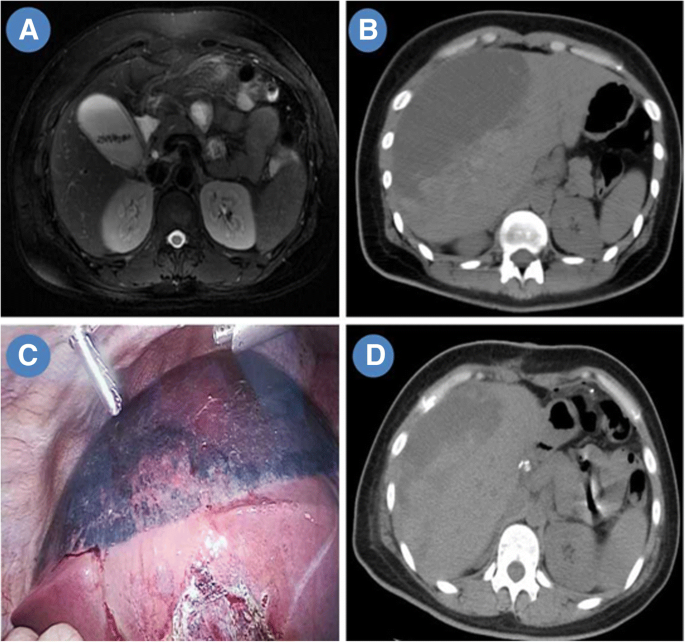

The patient was a 32-year old woman with a one-year history episodes of cholecystitis treated conservatively. She did not have any other disease history. After an abdominal magnetic resonance imaging that confirmed multiple gallbladder stones (Fig. 1a), an elective LC was performed without intra-operative complications. The recovery was uneventful and the patient was discharged two days after operation. On the second day after discharge, the patient developed severe right upper abdominal pain and she was sent to our emergency department at 8:30 pm. At arrival, her heart rate was 110 bpm and the blood pressure was 80/55 mmHg. The hemoglobin dropped to 86 g/l from 127 g/l. The CT scan showed a 10.9 × 12.5 × 6.6 cm ISH in the right liver without obvious free fluid in abdominal cavity (Fig. 1b). Two hours after fluid resuscitation including 2 U red blood cell, the hemoglobin further declined to 78 g/l and the hemodynamics remained unstable. The abdominal pain was not relieved, after intravenous analgesics. A Doppler ultrasound was performed, two hours later and it found the hematoma had increased in size. Active intrahepatic bleeding was suspected. We called radiologist for consultation, however, the interventional angiography and embolization was not available at mid night. We explained the potential risk of sudden rupture of hematoma during conservative methods which may cause sudden death, to the patient and her relatives. After careful consideration of the continuous decline of hemoglobin, unstable hemodynamics after fluid resuscitation, we explained our surgical plan to the patient and her relative. We planned to perform laparoscopic exploration at first, if the hematoma continued to expand, we would evacuate or drain it, if not, we would put a drainage tube under liver which could serve as an early warning of rupture. The patient requested surgical method to reduce the risk of sudden death. Therefore, an emergency laparoscopic exploration was performed under general anesthesia. The ISH was confirmed (Fig. 1c). Four U red blood cell and 400 ml fresh frozen plasma were transfused. After fluid resuscitation and blood transfusion, her hemodynamic became stable. During the 3-h intra-operative observation, the hematoma did not expand. Therefore, a non-sucking drainage tube was placed under the liver and she was sent to ICU ward. Next morning, she was transferred to the ordinary ward. The upper abdominal pain gradually relieved. Five days after the laparoscopic exploration, another CT scan showed that the hematoma was largely resolved and we removed drain tube (Fig. 1d). She was discharged, 10 days after readmission.